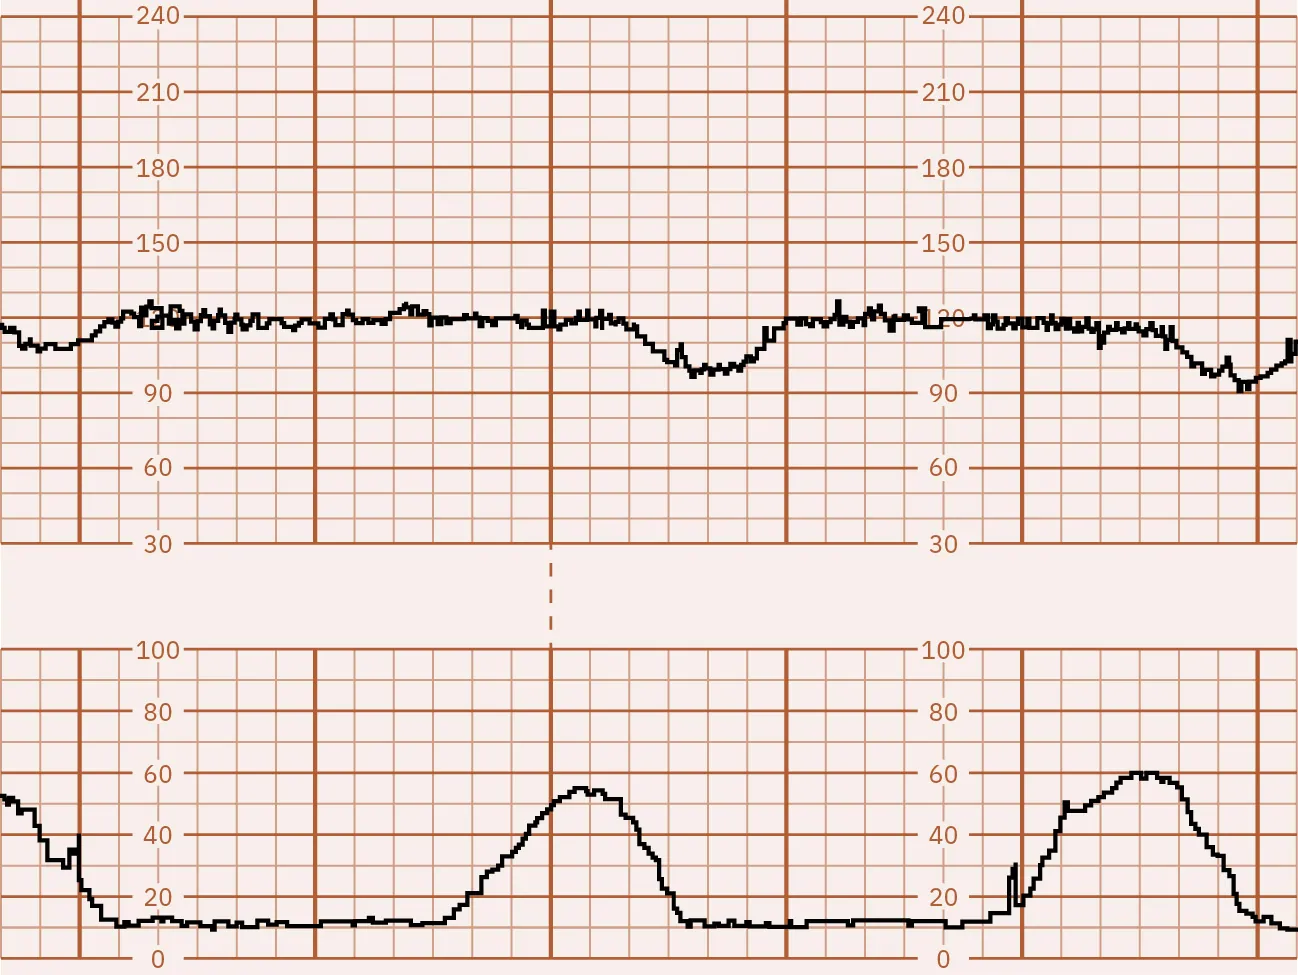

Contraction Stress Test

A contraction stress test (CST) may be recommended if the NST is nonreactive, or unclear, when ultrasound for a BPP is not available. The CST is not widely used anymore due to the availability of a BPP, which is less invasive. A contraction stress test evaluates the response of the fetal heart rate to uterine contractions. During contractions, there is a decrease in the oxygenation of the fetus. If the fetus lacks a reserve of oxygen (demonstrating uteroplacental insufficiency), then a nonreassuring FHR pattern is noted during contractions (ACOG, 2021c).

A contraction stress test allows the provider to see how the fetal heart rate reacts when the uterus contracts. During this test, the external fetal and contraction monitor is applied. (See Chapter 16 Electronic Fetal and Uterine Contraction Monitoring for more information on external fetal monitoring.) The health-care provider will order oxytocin (Pitocin) or have the pregnant person perform nipple stimulation to make their uterus contract. The expected uterine contraction pattern for a CST is at least three contractions lasting for a minimum of 40 seconds each within a 10-minute period. If the patient is already experiencing sufficient spontaneous contractions, there is no need for uterine stimulation. However, if there are fewer than three contractions of 40 seconds each within 10 minutes, nipple stimulation or intravenous oxytocin will be used to induce contractions. A spontaneous CST can be considered if the necessary number and strength of contractions are achieved within the 10-minute time frame (ACOG, 2019a).

The CST test results are divided into several categories:

• Negative: This means there are no late or significant variable decelerations (Figure 13.11).

Fetal monitor tracing graphic depicting negative CST. Top strip remains stable during spikes in the lower strip.

Figure 13.11 Negative CST In this illustration, the FHR baseline is 130 and is at the top of the graph. Contractions are recorded on the bottom. This strip shows that with each contraction, or peak, at the bottom, the heart rate remains stable, which makes it a negative result. (attribution: Copyright Rice University, OpenStax, under CC BY 4.0 license)

Fetal surveillance with a CST is done to identify the fetusโ€™s risk of hypoxic injury or death so that appropriate intervention can be done to prevent an adverse outcome if possible. It can also identify normally oxygenated fetuses to allow pregnancy to continue safely and avoid unnecessary intervention (ACOG, 2021d).

The nurse can help prepare the pregnant person for a CST by explaining why the test is recommended, answering any questions, and describing what will happen during the test. Prior to the CST, the nurse will need to get a baseline tracing, and the nurse will monitor the tracing afterwards while a plan of care is being determined. The provider will review the results directly after the test is completed and discuss with the pregnant person if continuing the pregnancy, further testing, or delivery is the best plan.